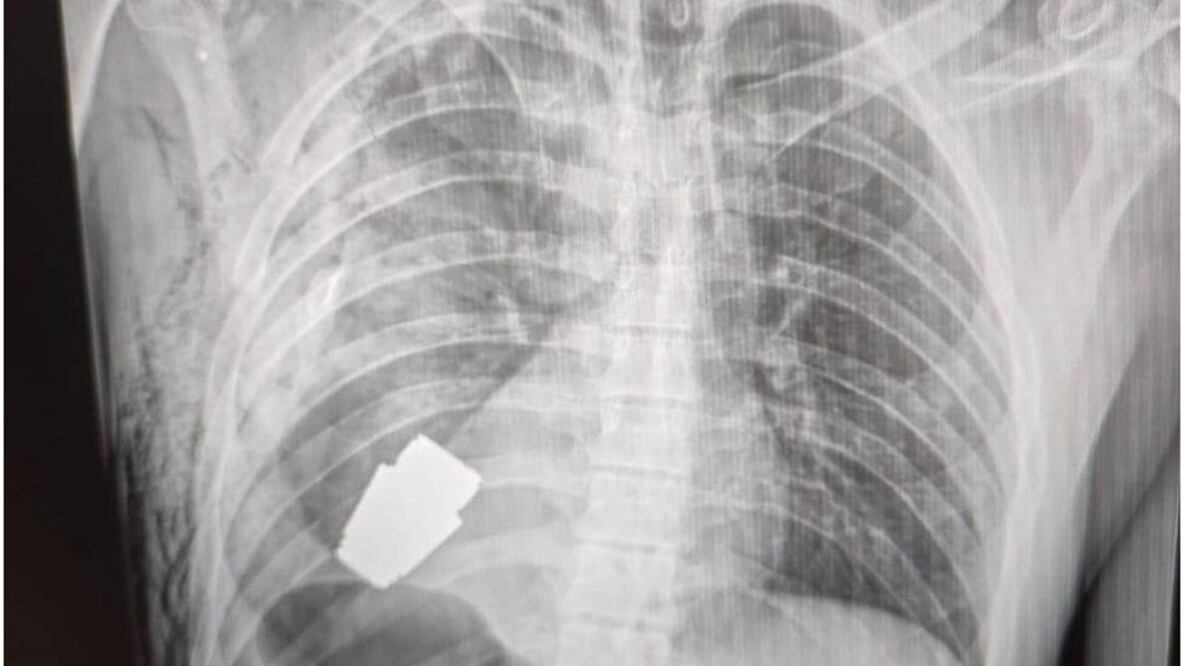

El gobierno ucraniano describió como un "susto afortunado" la terrible experiencia por la que tuvo que pasar un soldado herido, a quien le extrajeron con éxito una granada que se encontraba en su pecho.

El resultado de la delicada operación fue dado a conocer por la viceministra de Defensa, Hanna Maliar, quien publicó en redes sociales que "no todas las heridas en la zona del corazón son letales".

El fragmento de la granada de fabricación rusa que quedó alojado en el cuerpo del soldado tenía cuatro centímetros de diámetro y pesaba 275 gramos.

Lo que más impresiona a los analistas es cómo la granada permaneció sin detonar pese a mantenerse explosiva durante y después de la operación hasta que fue desactivada por los especialistas